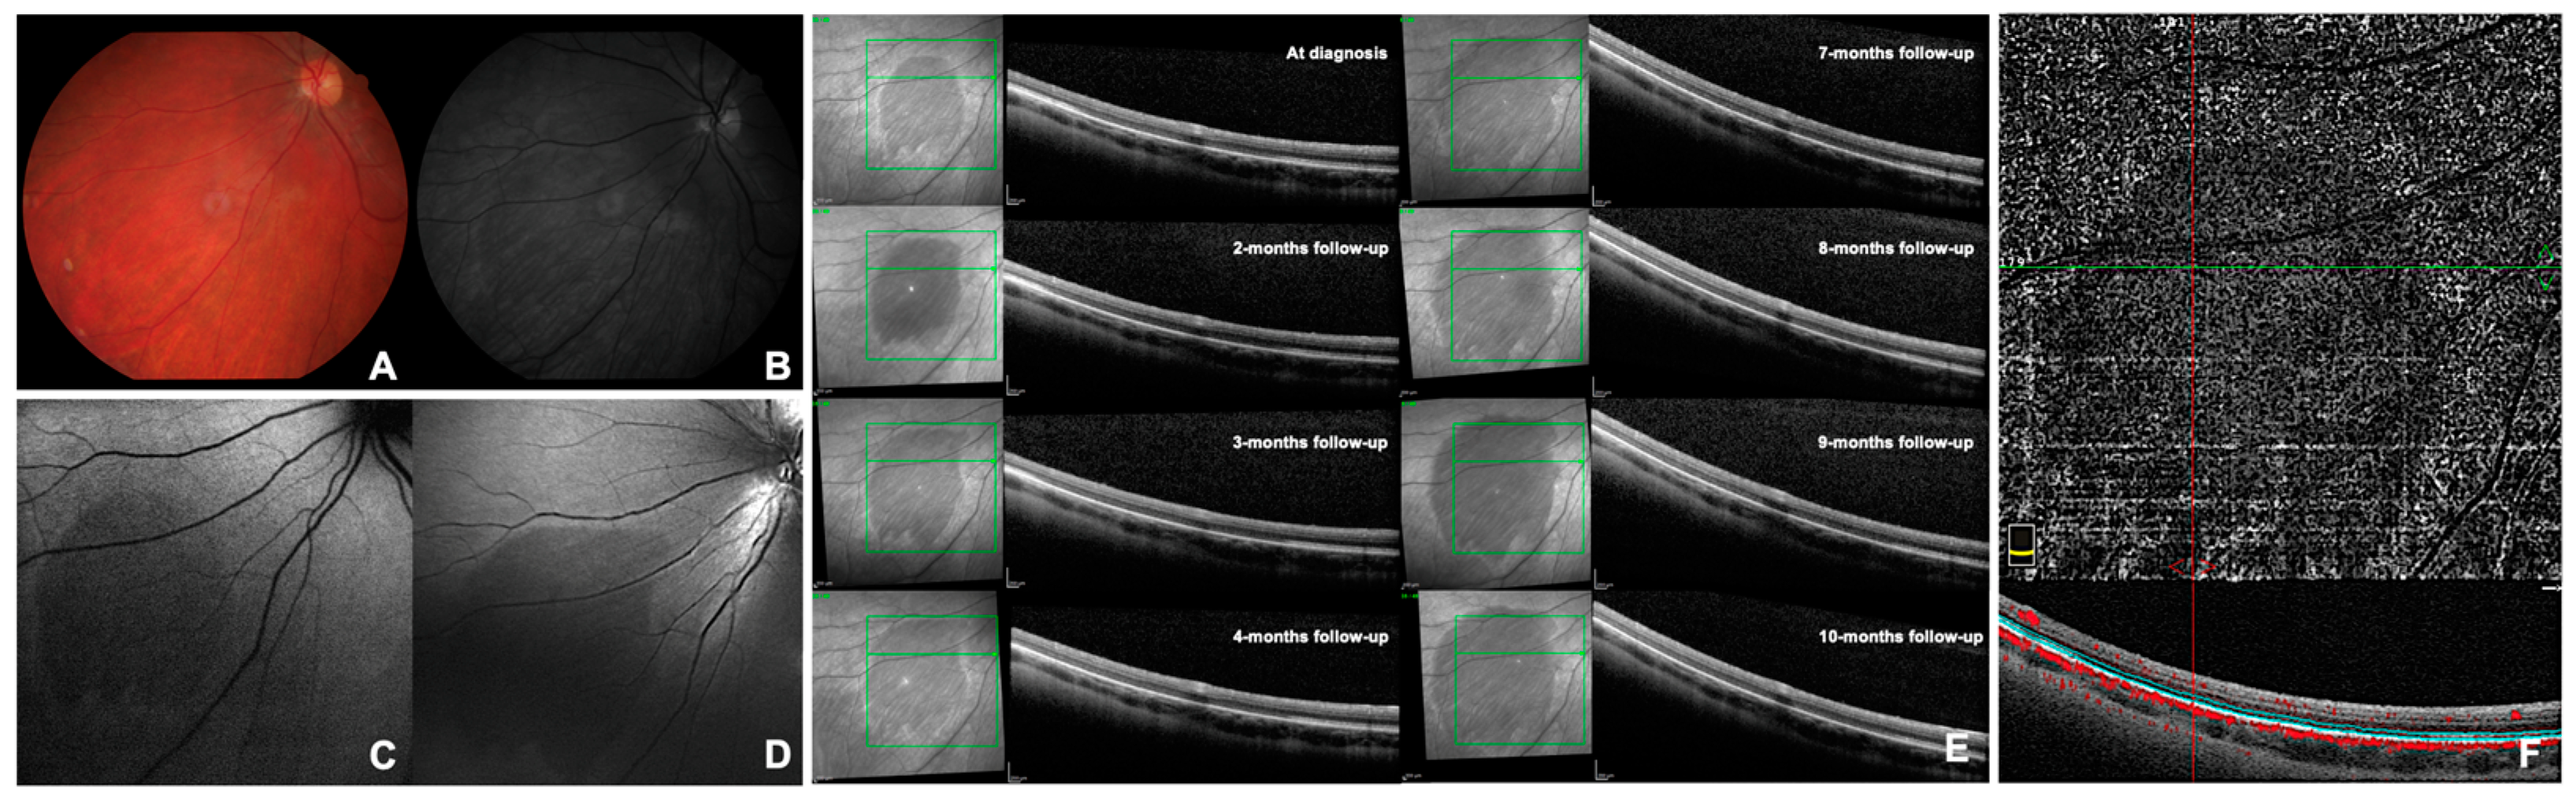

CASE 3. A 48-year-old Caucasian male presented to our Retina Center to perform FA to investigate optic neuropathy with a recent onset of microcystic macular edema in both eyes. He assumed ramipril for systemic hypertension and no drugs potentially toxic to the retina. The patient presented a BCVA of 0.1 logMAR (20/25) in the RE and hand motion in the LE. The patient was pseudophakic and a PreserFlo micro-shunt was present with effective filtrating blebs in both eyes. He assumed topical timolol, brimonidine, brinzolamide, and bimatoprost in both eyes for advanced glaucomatous optic neuropathy. The intraocular pressure was 9 mmHg in the RE and 10 mmHg in the LE. The patient had no clinical signs of intraocular inflammation. FA showed hypo-fluorescence of the optic disc in both eyes, perivascular leakage in the temporal periphery of the LE, and mild late-phase pooling in the macular area in both eyes. We related the microcystic macular edema to the advanced optic neuropathy. The patient did not present signs of epitheliopathy. A trapezoid-shaped area of approximately 4 papillary diameters, that remained hypo-fluorescent in all phases of the angiography, was highlighted in the inferior mid-periphery of the RE (Figure 2A). This area was barely visible in ophthalmoscopy as a dark spot but was better identifiable through red-free light; it was hypo-fluorescent on BAF and hypo-reflective at NIR and BR (Figure 2B). The lesion, diagnosed as DWP, corresponded to an attenuation of the reflectivity of the EZ band at the OCT scans (Figure 2C). OCT-A showed similar findings to Case 2 (Figure 2D). Brain magnetic resonance imaging showed signs of multifocal leukoencephalopathy of probable chronic microvascular nature. SITA-SAP revealed absolute and relative peripheral scotomas with a partial sparing of the central region in the RE, while the central area in the LE was involved. Visual field examinations did not allow for highlighting any signs attributable to the DWP spot. The patient has been diagnosed with microscopic polyangiitis associated with anti-neutrophil cytoplasmic antibody (p-ANCA). At the 6-month follow-up visit, the DWP lesion had decreased in size; the patient had started treatment with prednisone and methotrexate two months before.

Figure 2. Selected images of dark without pressure from Case 3 (see text). Panel (A) shows the mid-phase fluorescein angiography at the time of diagnosis. Panel (B) shows the blue reflectance at the time of the diagnosis. Panel (C) shows the infrared optical coherence tomography at the diagnosis and during the follow-up examination after 6 months. Panel (D) shows the optical coherence tomography angiography at the time of the diagnosis.